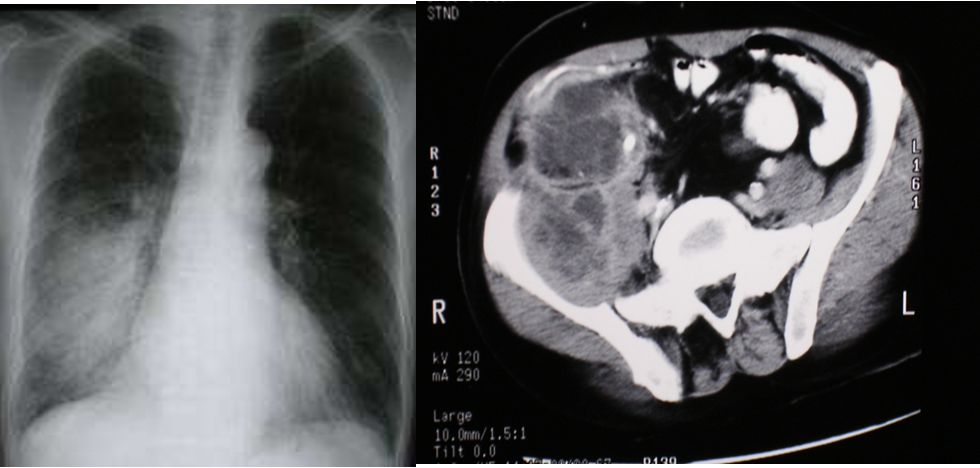

Common sites of infection:

- Lung (50-70%), (respiratory)

- abdomen (20-25%) ,

- urinary tract (5-7%),

- skin.